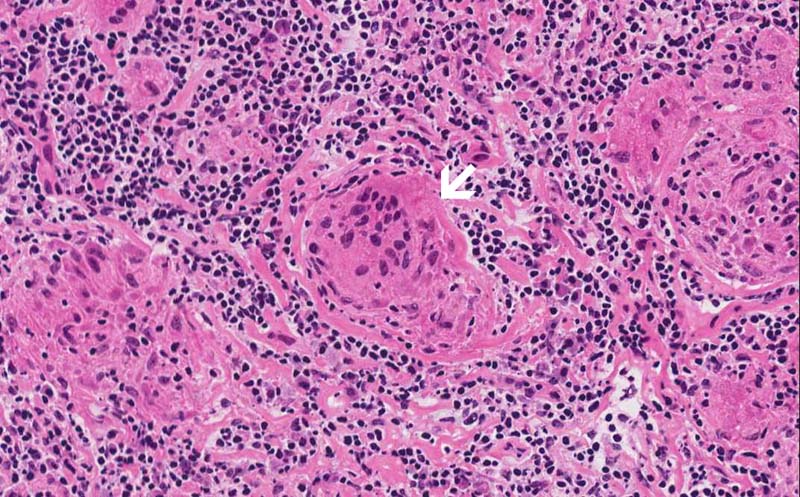

Area 1: Granulomas (arrow) are collections of histiocytes. These cells will be strongly reactive for antibody against CD68 or CD163 which mark histiocytes. Immunohistochemistry is useful when the granuloma is not as well defined or if there is a question that these cells may represent metastatic carcinoma. Granulomas in sarcoidosis is usually free of necrosis. Typically, they are not infiltrated by a substantial amount of lymphocytes and they are quite well defined from the surrounding lymphocytes. They also are more likely to be round or oval. In contrast, granulomas in tuberculosis are usually infiltrated by lymphocytes, much less well defined, more irregular in shape, and may have caseous necrosis.

• The salient histopathologic change is the replacement of the entire lymph node by non-necortizing granuloma (Area 1). Lymphocytes are present in between the granulomas. On examination with polarized light, no birefringent substances are present.

• Granulomas are roughly round to oval to irregular collections of histiocytes often with mutinucleated giant cells. They can be seen in multiple types of disease processes that include sarcoidosis, fungal infection, mycobacterial infections, berylliosis, foreign body, granulomatous changes of neoplasms particularly lymphomas and germ cell tumors, Wegerner's granulomatosis, and other conditions.Granulomatosis in sarcoidosis is usually non-necrotizing but necrosis may occur. Inclusions such as Asteroid bodies (Area 2) and Schaumann bodies can be seen in sarcoidosis. These inclusions are suggestive, however, non-diagnostic for sarcoidosis.